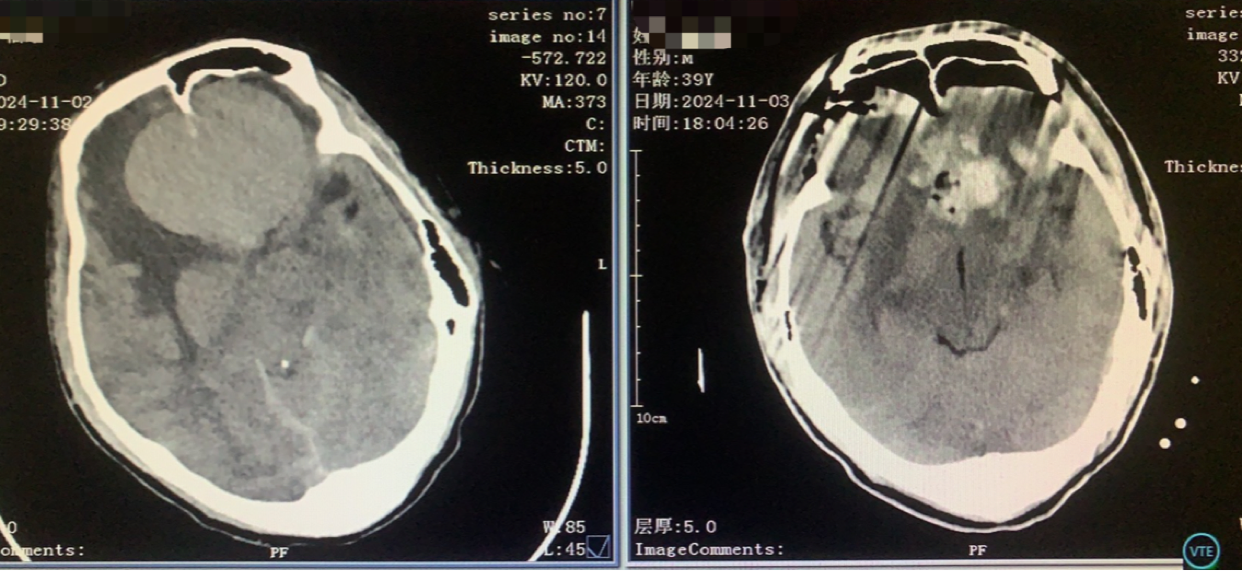

术前CT

神志昏迷双瞳散大对光反射迟钝入院,入院后甘露醇脱水加地米静滴后患者神经功能有改善,能摸索定位,瞳孔反射改善。考虑占位大直接切除可能出血多,拟术前栓塞处理,但造影发现栓塞不易风险高后放弃栓塞。

从右额分块切除处理大部分后,因条件所限单侧入路风险高遂加开左侧额外侧(骨窗较右侧小)。

术前术后对比